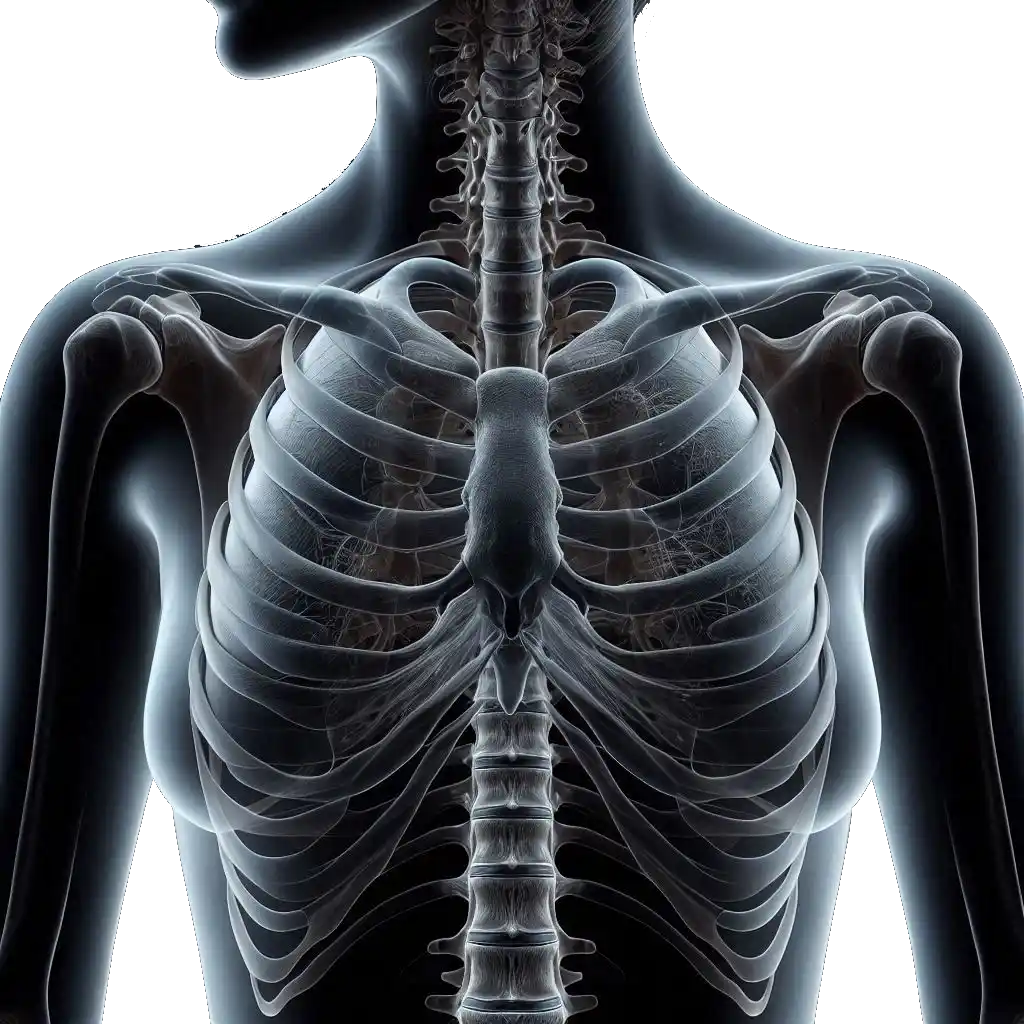

A veces hablamos de la zona lumbar como un “cilindro”. Esto significa que la columna vertebral se sitúa en el medio del cilindro y los músculos y vísceras alrededor de la columna crean una forma de cilindro. Cuando inhalamos y exhalamos y cuando “empujamos”, la presión y la geometría de este cilindro cambian. Esto afecta la estabilidad de la columna. La parte superior de este cilindro es un músculo llamado diafragma. El diafragma es quizás el músculo principal para la respiración, pero también juega un papel en la estabilidad de la columna y en la presión intraabdominal. Lógicamente, dado que el diafragma juega un papel en la estabilidad de la columna y en la respiración, ¡la respiración está vinculada a la estabilidad de la columna!

Los profesionales harían bien en incorporar esto en su tratamiento del dolor lumbar, ayudando a las personas a identificar patrones de respiración defectuosos y ofreciendo estrategias para promover mejores hábitos. En resumen, el énfasis debe estar en elevar y expandir la caja torácica durante la inspiración, teniendo en cuenta la biomecánica de la columna vertebral y los patrones de movimiento. ¡El diafragma es, de hecho, parte del equipo!